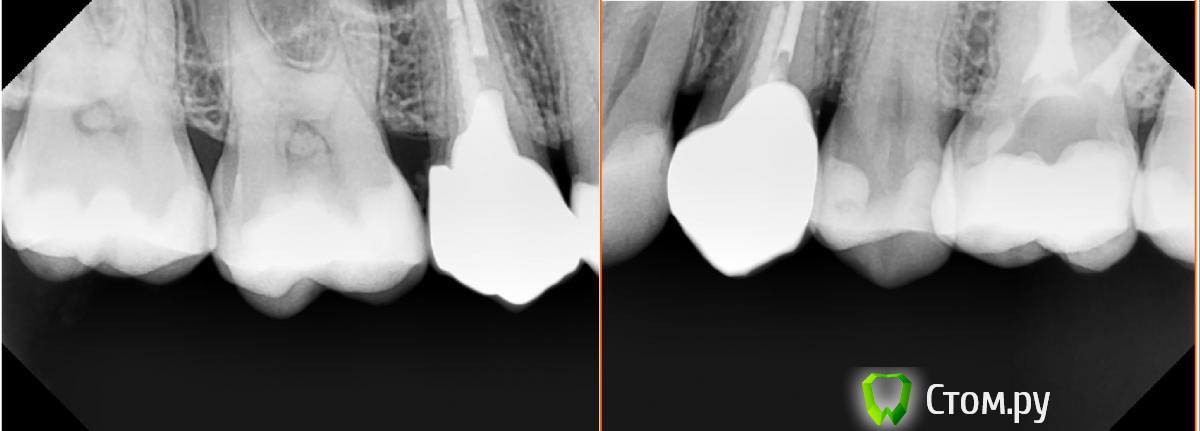

SDC Опубликовано 19 ноября, 2014 Поделиться Опубликовано 19 ноября, 2014 (изменено) Prettau, извините, не знаю, как редактировать название темы. Здравствуйте всем. В хирургическом много практиков, а по протетике - много теории)). Итак, разбавляю вино. (теория вечна)Протезирование премоляров коронками Преттау с нанесением керамики вестибулярно.Много фото, прошу прощения, поэтому без радикала, превью. Наверное даже так лучше, потому, что по клику откроются не сжатые фото, а радикал жмет.Протезирование в течение 2 недель. Фиксация на фуджи, без коффердама, но в сухих условиях (коффер не поставить по причине глубокий дистальной границы препарирования на обоих премолярах - глубокий кариес проксимальных поверхностей в анамнезе)Рг-контроль на предмет остатков цемента и на последнем фото удаленные излишки цемента на перчатке. Изменено 19 ноября, 2014 пользователем SDC 7 Ссылка на комментарий

Lolopop Опубликовано 19 ноября, 2014 Поделиться Опубликовано 19 ноября, 2014 за что такая любовь к штифтам с резьбой?) работа красивая) Ссылка на комментарий

Lolopop Опубликовано 19 ноября, 2014 Поделиться Опубликовано 19 ноября, 2014 каждый выбирает что ему по душе) а мне титановые штифты не нравятся, моя любовь это КШВ. подумал о любви - потому что на обоих зубах на снимке Ваши ЛЮБИМЫЕ штифты))) смущает в титановых штифтах не резьбовая нарезка , а фиксация на цемент...вернее именно та чать штифта которая остается в коронке, ведь она головка штифта вместе с цементом создает культю, а культя из штифта и сица как то не мне) Ссылка на комментарий

SDC Опубликовано 19 ноября, 2014 Автор Поделиться Опубликовано 19 ноября, 2014 (изменено) каждый выбирает что ему по душе) а мне титановые штифты не нравятся, моя любовь это КШВ. подумал о любви - потому что на обоих зубах на снимке Ваши ЛЮБИМЫЕ штифты))) смущает в титановых штифтах не резьбовая нарезка , а фиксация на цемент...вернее именно та чать штифта которая остается в коронке, ведь она головка штифта вместе с цементом создает культю, а культя из штифта и сица как то не мне)Ясно. Дело в том, что при восстановлении литой вкладкой есть много моментов, при которых может быть нарушен герметизм корневого канала:- период с временной пломбой- слепок- период с временной пломбой- примерка и фиксация (если проводить этот этап без коффердама)Мы зависимы от точности, предоставляемой лабораторией. В случае, если не согласны:- повторный слепок- период с временной пломбой- примерка и фиксация Все это время (до месяца) пациент "без зуба" или со штифтовой временной конструкцией, вероятность разгерметизации которой в разы больше, чем у временной пломбы. В зубах фронтальной группы - это СВШ - они становятся любимыми.В зубах боковой группы - титановые.Я долгое время думал, что иду "своим" путем (очень часто от коллег встречались возражения по поводу применения титановых постов для билдапов) вдруг, недавние новости от Манье показали, что он тоже (или я тоже) позитивно относится к титановым штифтам с композитными корами для билдапов. Изменено 19 ноября, 2014 пользователем SDC Ссылка на комментарий